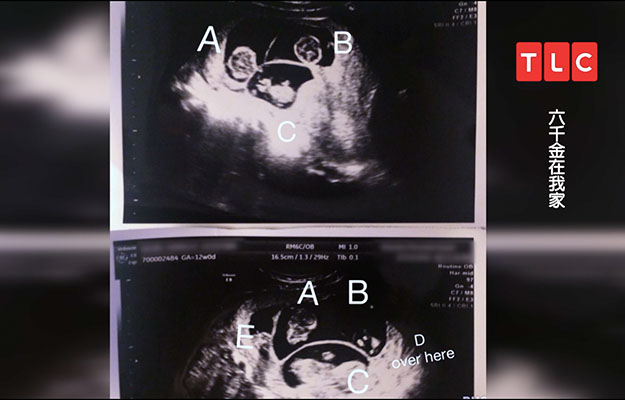

其實女主人丹妮爾一開始是排出4顆卵子,其中一顆卵子分裂,導致原本的四胞胎變成五胞胎,其中一對是同卵雙胞,長相一模一樣。